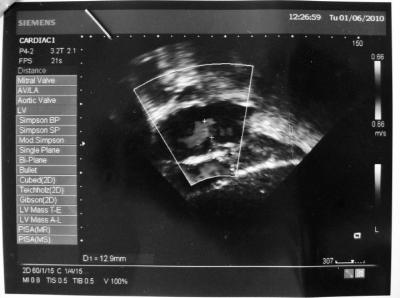

সাব্বির নিজে পড়াশোনার বেপারে খুব সিরিয়াস, স্টুডেন্ট হিসাবে খুব ভাল কিন্তু মাঝে কিছু দিন লেখা পরা বন্ধ রাখতে হইছে চিকিৎসার জন্য। জন্ম থেকে হার্ট এ ছিদ্র আছে, আর সব চেয়ে বেশি আছে সংসার এর অভাব...তাই দেখতেও রোগা রোগা লাগে...গল্প করে- আগে নাকি দেখতে অনেক সুন্দর,ফরসা ছিল!

হার্ট এর ছিদ্রটাকে বন্ধ করার জন্য নিজের সহ আরো দুই ভাই-বোন এর লেখাপড়া এখন বন্ধ..... কিন্তু টাকার জন্য ছিদ্রটা বন্ধ করা যাচ্ছে না...বাংলাদেশের সব চেয়ে বড় হস্পিটাল- জাতীয় হৃদরোগ ইনস্টিটিউট ও হস্পিটাল (সাব্বির মনে করে এটাই বাংলাদেশ এর সব চেয়ে বড় হস্পিটাল) এর ডাক্টার রা বলে দিছেন মিনিমাম ৬০,০০০-৭০,০০০/- টাকা লাগবে (প্রাইভেট হস্পিটাল এ আরো অনেক বেশি লাগত)......কিন্তু সাব্বির এর ফাদার এর জন্য এই টাকা টা যোগার করা খুবই টাফ্।